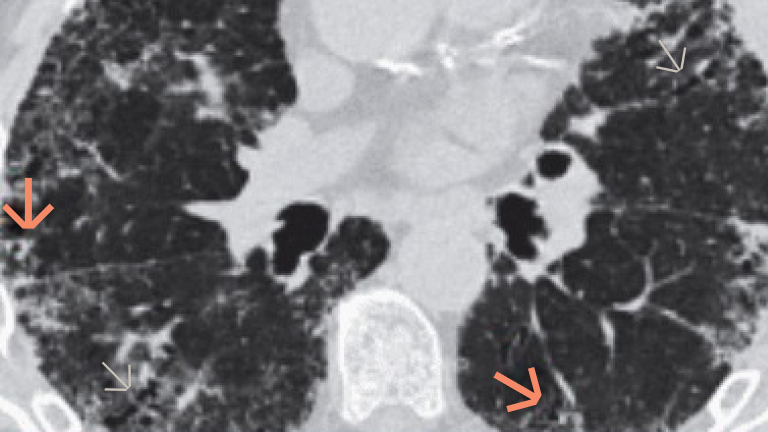

Skuteczniej rozpoznawaj włókniejącą ILD. Ten atlas może pomóc w diagnostyce ILD, ułatwiając rozpoznawanie kluczowych wskazówek i typowych cech w obrazach HRCT klatki piersiowej i w badaniu histopatologicznym wycinków z chirurgicznej biopsji płuca.

Ścisła współpraca pomiędzy reumatologiem, pulmonologiem, radiologiem i patologiem jest ważna w kontekście rozpoznania ILD u pacjentów z CTD.11 Badanie HRCT w połączeniu z omówieniem na forum wielodyscyplinarnym może umożliwić pewne rozpoznanie ILD w przebiegu CTD.12–14 Rozpoznanie wielodyscyplinarne wiąże się z wyższym poziomem pewności diagnostycznej i lepszą zgodnością pomiędzy obserwatorami w porównaniu z sytuacją izolacji poszczególnych ról.14

HRCT W POŁĄCZENIU Z OCENĄ WIELODYSCYPLINARNĄ DAJE WYSOKĄ PEWNOŚĆ ROZPOZNANIA ILD U PACJENTÓW Z RZS17-19

Podejście wielodyscyplinarne, obejmujące co najmniej reumatologa, pulmonologa i radiologa, poprawia diagnostykę i postępowanie w RZS-ILD.17,20 Zaleca się omówienie wielodyscyplinarne w celu potwierdzenia rozpoznania i oceny stopnia ciężkości RZS-ILD na podstawie rozległości ILD w badaniu HRCT oraz wartości DLCO.21